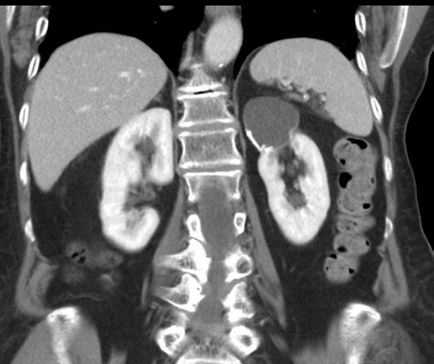

A cisztás vesekárosodás fejezhető ki több lézió a test szöveteiben, amelyek úgy néznek ki, mint egy buborék kinövések átlátszó vagy gennyes tartalom. Fent látható, úgy néz ki, mint egy ciszta a vese fotók, alatt és azt mutatják, hogy minek az alapján, hogy ezt a fajta diagnózis a diagnózis MRI, CT és az ultrahang.

Mint látható a képen, a vese ciszta befolyásolhatja a bal és jobb oldalán egy párosított szerv, attól függően, hogy a betegség típusától és annak okait.